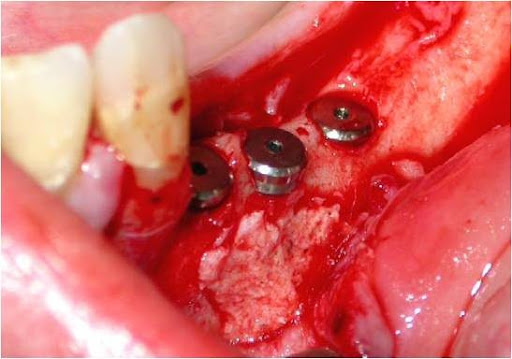

Uma vez localizado o canal mandibular sua parede é cuidadosamente retirada, liberando-se progressivamente o feixe neurovascular. Eventualmente, por uma outra técnica há necessidade de se realizar a transposição do nervo incisivo para se obter um afastamento satisfatório do NAI. Após o afastamento do feixe, realiza-se a fixação dos implantes, seguindo o protocolo correspondente, utilizando-se da cortical basal ou não, para obter uma melhor estabilidade inicial (24, 30) (Figs. 8, 9 e 10). Na seqüência o NAI é acomodado passivamente na loja óssea quando apenas lateralizado (12, 29).

Existem ressalvas quanto à colocação de materiais implantares pela possibilidade de infecções e, uma vez que o defeito ósseo é coberto completamente pelo periósteo haverá reparação dessa área (09). Alguns autores indicam a colocação de membranas para dar maior sustentação do retalho sobre a janela formada (30). O preenchimento da cavidade com osso particulado assim como o recobrimento do local com uma barreira biológica é um procedimento que traz bons resultados (Figs. 11 e 12).

Figs. 11 e 12 – O osso particulado preenchendo perfeitamente a cavidade e, sendo recoberta toda a região com a barreira biológica.